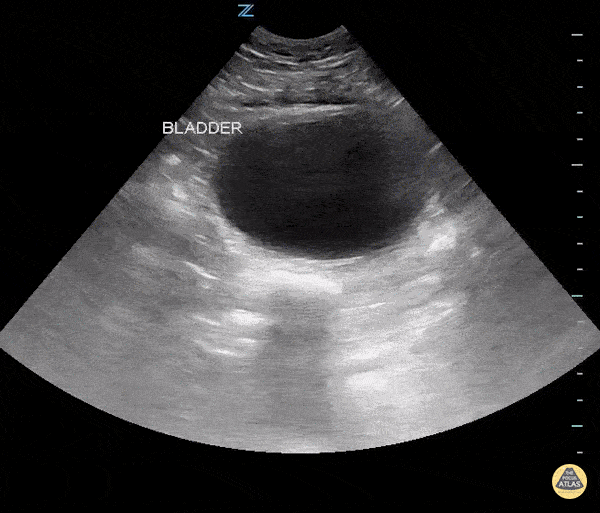

In this transverse, transabdominal ultrasound one can see a full bladder and posterior to that a uniformly enlarged prostate suggesting urinary retention secondary to BPH. Sukh Singh, MD